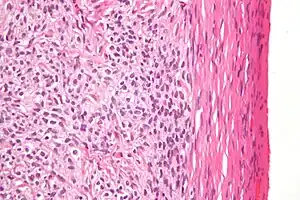

Low magnification micrograph of a thecoma showing compression of the ovarian cortex (right of image). H&E stain.

Microscopically, the tumour cells have abundant lipid-filled cytoplasm.